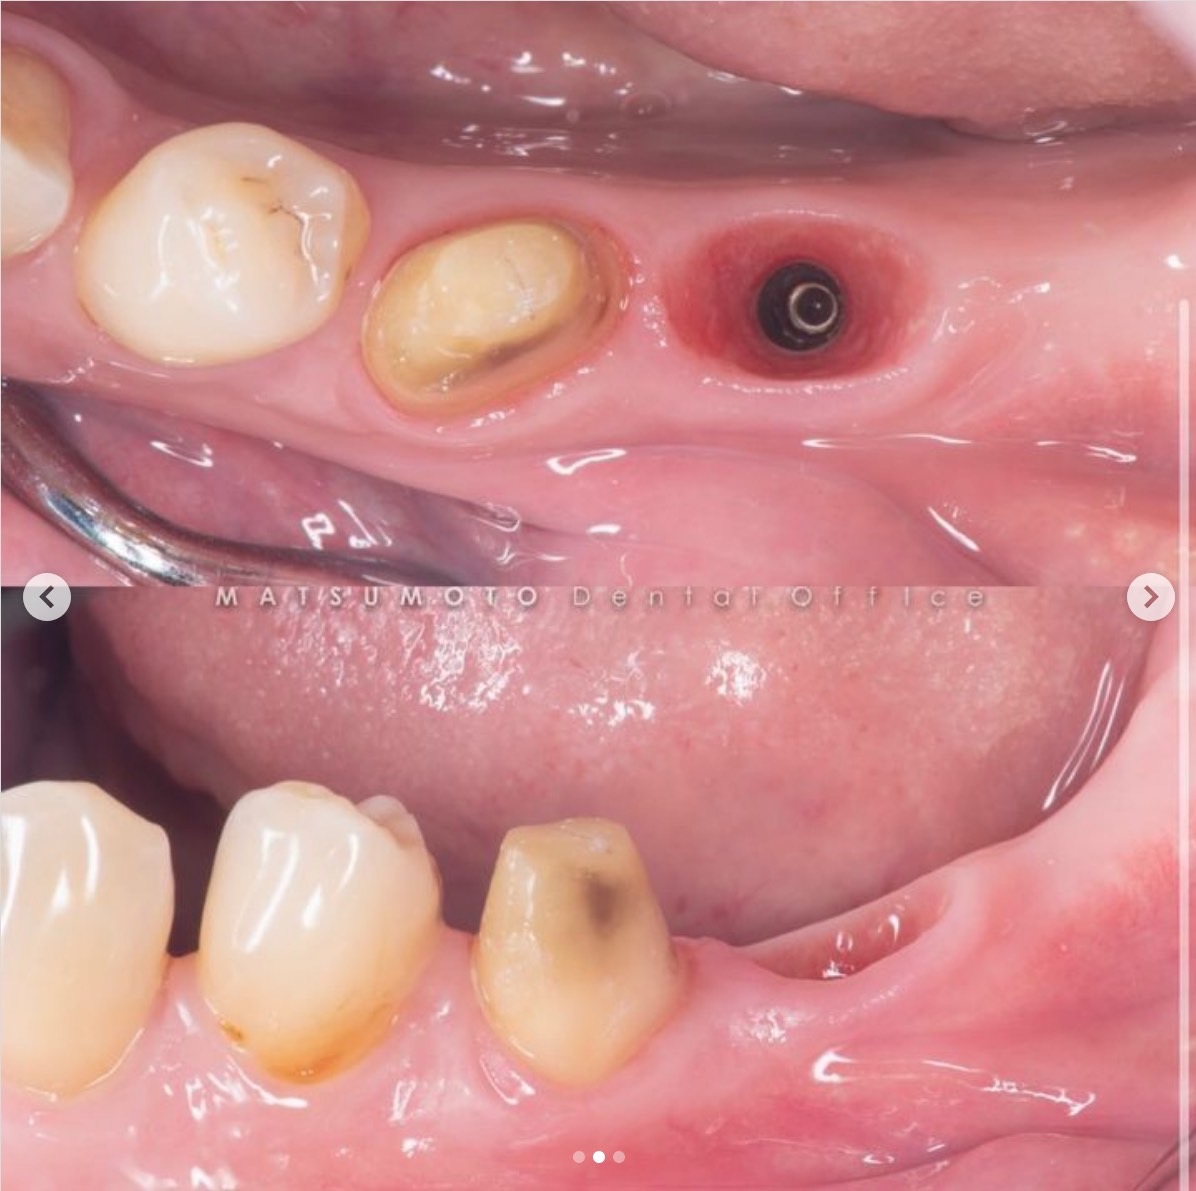

術前の診査診断

術前写真

下顎:欠損の両側の歯は健康な状態。

レントゲン写真

下顎:骨の高さは十分にあるが、幅が少し足りない状態である。

治療を終えて

最終補綴

下顎:フルジルコニアスクリューリテイン

治療のリスクと副作用

治療期間:3ヶ月

治療費:¥462,000(税込)

リスク:インプラントを正確に入れることによって、セラミックの破折を最小限に抑えることができます。